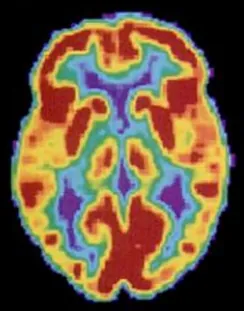

Positron emission tomography (PET) scans create pictures of the living, active brain (Figure 3.27). An individual receiving a PET scan drinks or is injected with a mildly radioactive substance, called a tracer. Once in the bloodstream, the amount of tracer in any given region of the brain can be monitored. As brain areas become more active, more blood flows to that area. A computer monitors the movement of the tracer and creates a rough map of active and inactive areas of the brain during a given behavior. PET scans show little detail, are unable to pinpoint events precisely in time, and require that the brain be exposed to radiation; therefore, this technique has been replaced by the fMRI as an alternative diagnostic tool. However, combined with CT, PET technology is still being used in certain contexts. For example, CT/PET scans allow better imaging of the activity of neurotransmitter receptors and open new avenues in schizophrenia research. In this hybrid CT/PET technology, CT contributes clear images of brain structures, while PET shows the brain’s activity.

A brain scan shows different parts of the brain in different colors.

Figure 3.27 A PET scan is helpful for showing activity in different parts of the brain. (credit: Health and Human Services Department, National Institutes of Health)